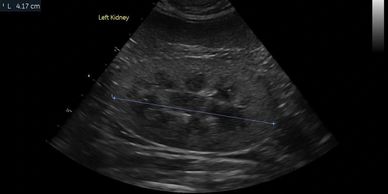

An evaluation of every abdominal organ for size, margination, echotexture, and neoplasia. All standard abdominal measurements will be acquired according to the current ACVR protocol

Screening of the the urinary and biliary tract for stones, accumulated material, obstructions, or evidence of congenital defects